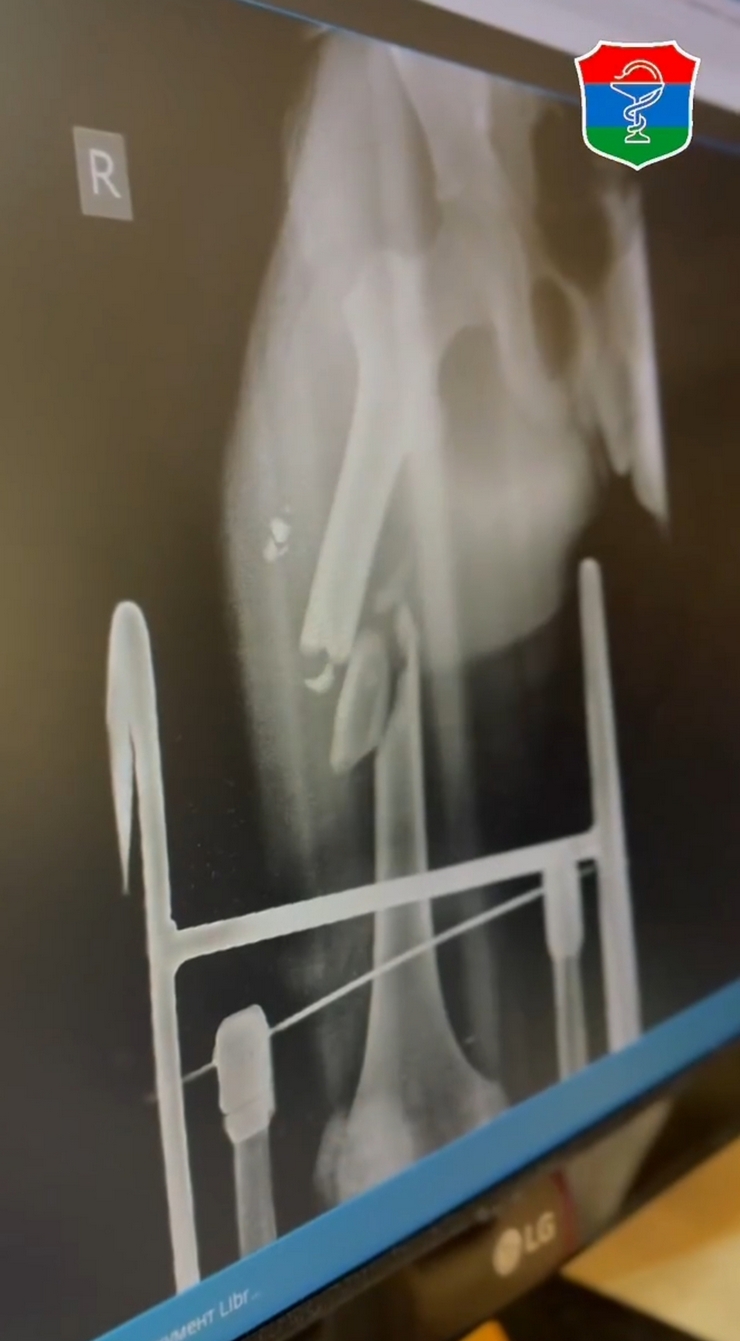

С наступлением тепла дети с травмами, полученными при езде на питбайках, самокатах и велосипедах, поступают в Детскую республиканскую больницу им. И.Н. Григовича почти каждый день. Фото рентгеновских снимков из больницы ужасают.

— Участились случаи с детьми младшего возраста, которые не допускаются до управления питбайками. Дети получают тяжелые черепно-мозговые травмы, тяжелые скелетные травмы, которые требуют оперативного лечения. Чаще всего дети на питбайках без средств индивидуальной защиты, без шлемов, без наколенников, налокотников. Из-за этого травмы тяжелые, — рассказал травматолог-ортопед Дмитрий Иванович в видео, опубликованном главой минздрава Карелии Михаилом Охлопковым.